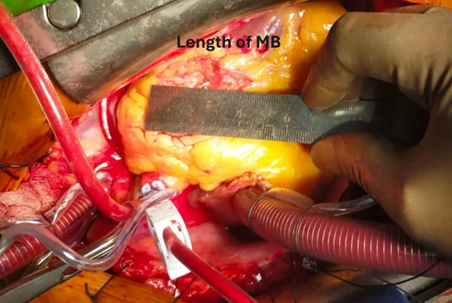

Then aorta was cross clamped and heart was arrested with antegrade cold-blood cardioplegia. After that to inspect epicardial surface of heart for intramyocardial LAD, was easily detected. Epicardial incision was given over the normal site of LAD coronary artery with 15 size surgical blade. Then dissection was extended proximally into the bridging portion of LAD coronary artery with the dissection of epicardial fat and underlying muscle or myocardial bridge with the help of Potts scissors and Electrocautery. The length of the myocardial bridge was about 4.5 cm. Careful dissection was done to avoid damage to the LAD coronary artery and its branches such as diagonal artery and to avoid injury to right ventricle. During dissection of epicardial fat and outer part of myocardial bridge electrocautery or Liga clip were used for hemostatic purpose.

Figure 10: Length of Myocardial Bridge.